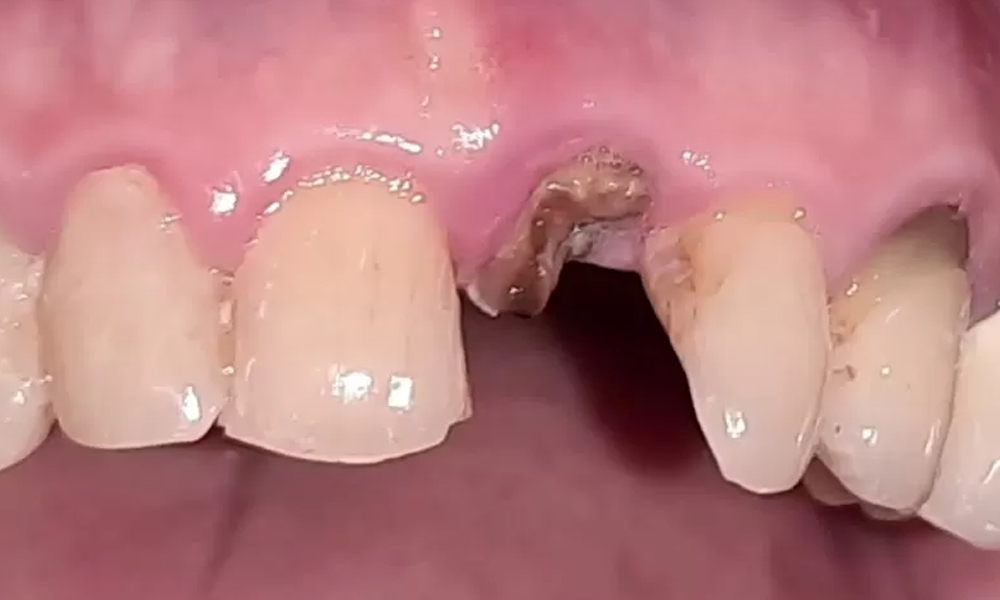

پس از گفتگوی اولیه، نوبت به ارزیابی بالینی و تصویربرداری تشخیصی میرسد. پزشک با دقت دهان، دندانهای باقیمانده، سلامت لثه و فضای مورد نظر برای ایمپلنت را معاینه میکند. در بسیاری از کلینیکهای مجهز تهران، یک عکس رادیوگرافی ساده (پانوراما) نیز در همان جلسه و به صورت رایگان گرفته میشود تا وضعیت استخوان فک، ریشه دندانهای مجاور و ساختارهای حیاتی به وضوح دیده شود. پس از گردآوری این اطلاعات کلیدی، پزشک تمام یافتهها، گزینههای درمانی، مراحل دقیق، زمانبندی، برندهای پیشنهادی و یک برآورد هزینه شفاف را به زبان ساده برای شما توضیح میدهد. اینجاست که شما میتوانید همه سوالات خود را بپرسید. مرحله نهایی، جمعبندی و ارائه برنامه درمانی مکتوب است و پس از آن، بدون هیچگونه تعهدی، میتوانید با آرامش در مورد ادامه کار تصمیم بگیرید. این ساختار منسجم، تضمین میکند که هیچ نکتهای در تاریکی نمانده و شما با چشمی باز وارد فرآیند درمان شوید.

۲. معاینه تخصصی و بالینی دهان

- یک بررسی بصری و فیزیکی دقیق از وضعیت لثهها، دندانهای باقیمانده و فضای خالی انجام میشود.

- سلامت لثه از نظر بیماریهای پریودنتال (عفونت لثه) ارزیابی میشود.

۳. تصویربرداری رایگان و تفسیر حرفهای (اغلب پانوراما)

- در اکثر کلینیکهای مجهز، یک عکس رادیوگرافی پانورامابه صورت رایگان گرفته میشود.

- پزشک این عکس را مانند یک نقشه راه برای شما تحلیل میکند.

- کیفیت، تراکم و ارتفاع استخوان فک به وضوح ارزیابی میشود.

- موقعیت اعصاب مهم و سینوسها مشخص میگردد.

- هدف: ارزیابی علمی و دقیق از زیرساخت استخوانی و پیشبینی نیاز به اقدامات تکمیلی مثل پیوند استخوان.